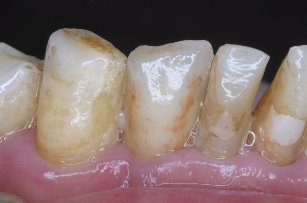

圖三為拔除之下顎側門齒,可見牙根處仍有許多的牙結石,因此治療無望,圖四為立即植牙後的情形,這時流血已完全停止,而齒槽骨與人工植第之縫隙再使用合成人工骨粉修復之,圖五為一週後牙肉之恢復情況

圖五 |